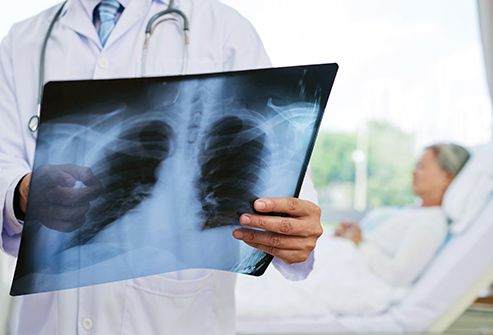

10. Viêm phổi

Những người trên 50 tuổi có nguy cơ mắc loại bệnh viêm phổi do vi khuẩn, không phải do vi rút gây ra cao hơn. Được gọi là viêm phổi do phế cầu khuẩn, nó có thể nguy hiểm đến tính mạng. Người lớn tuổi thường mắc bệnh này hơn vì hệ thống miễn dịch của cơ thể bạn yếu đi khi bạn già đi. Nhưng có loại vắc xin giúp phòng bệnh và CDC khuyến nghị chúng cho tất cả mọi người trên 65 tuổi.